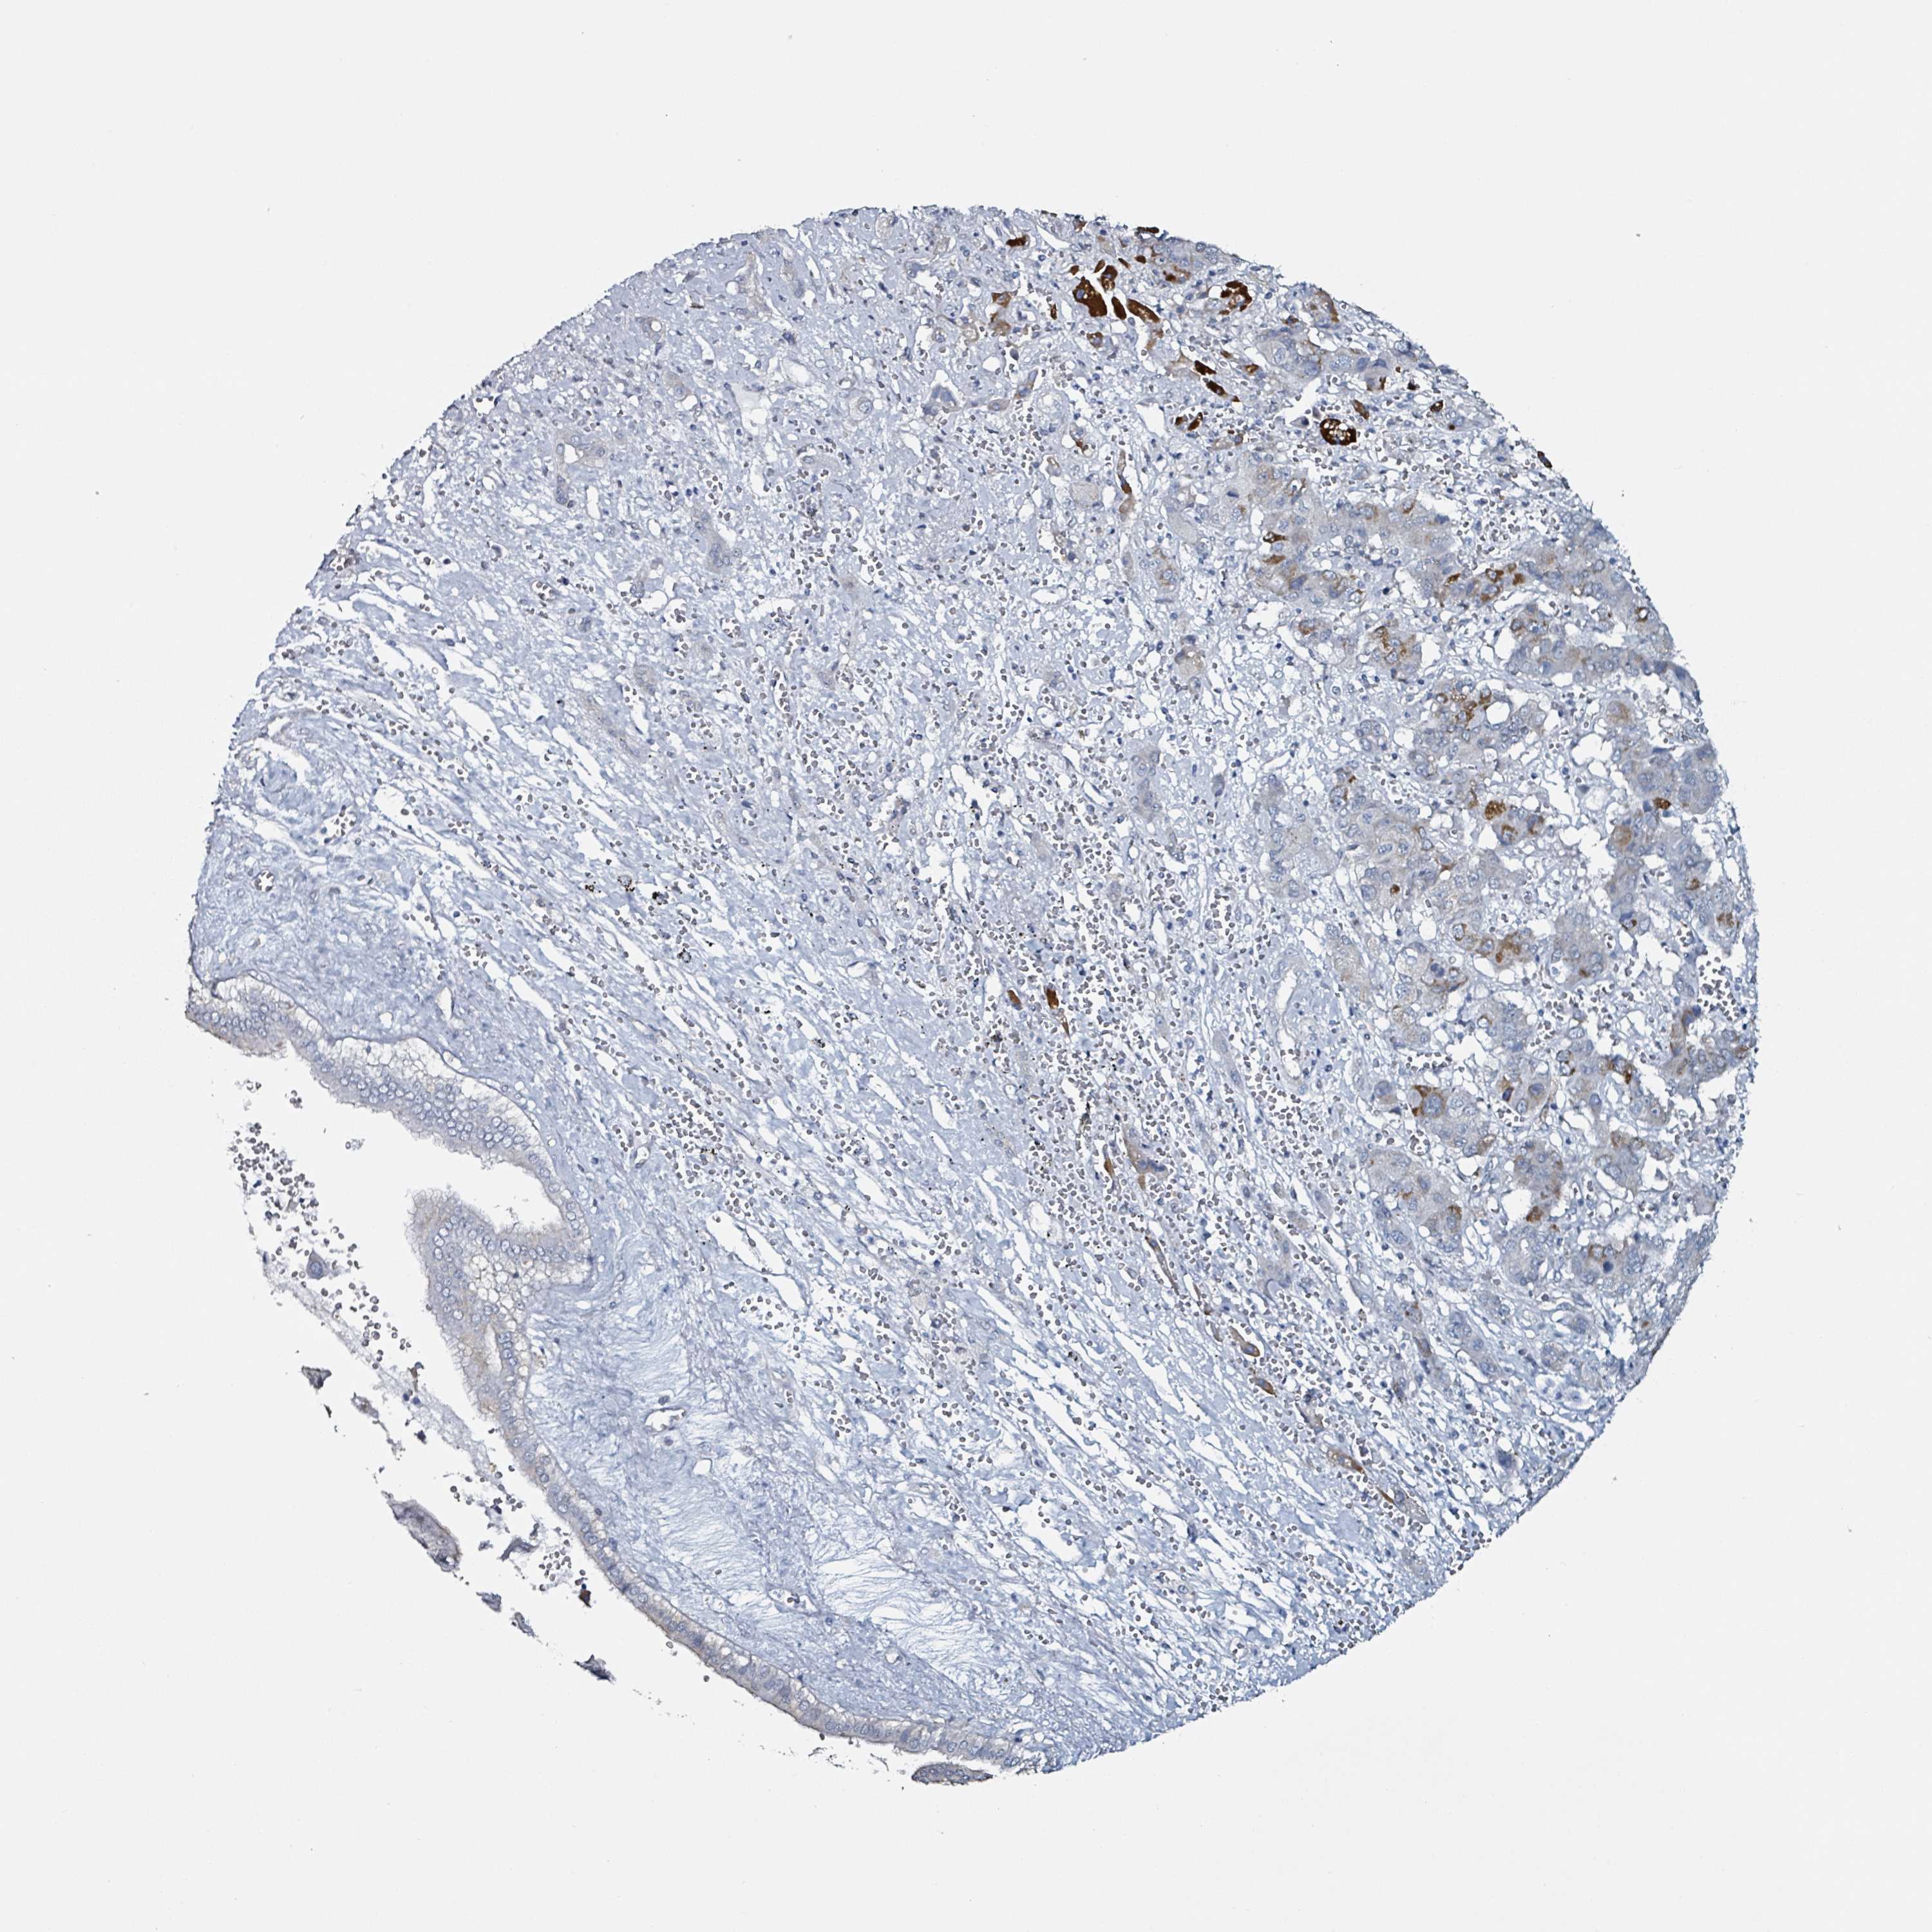

LIVER CANCER - Protein expressioni

A mouse-over function shows sample information and annotation data. Click on an image to view it in a full screen mode. Samples can be filtered based on level of antibody staining by selecting one or several of the following categories: high, medium, low and not detected. The assay and annotation is described here.

Note that samples used for immunohistochemistry by the Human Protein Atlas do not correspond to samples in the TCGA dataset.

Antibody stainingi

Antibody staining in the annotated cell types in the current human tissue is reported as not detected, low, medium, or high, based on conventional immunohistochemistry profiling in selected tissues. This score is based on the combination of the staining intensity and fraction of stained cells.

Each image is clickable and will lead to virtual microscopy that enables deeper exploration of all samples and also displays staining intensity scores, fraction scores and subcellular localization as well as patient and tissue information for each sample.

Antibody HPA051328

Staining

High

Medium

Low

Not detected

Intensity

Strong

Moderate

Weak

Negative

Quantity

>75%

75%-25%

<25%

None

Location

Nuclear

Cytoplasmic/membranous

Cytoplasmic/membranous,nuclear

Cholangiocarcinoma

Carcinoma, Hepatocellular, NOS